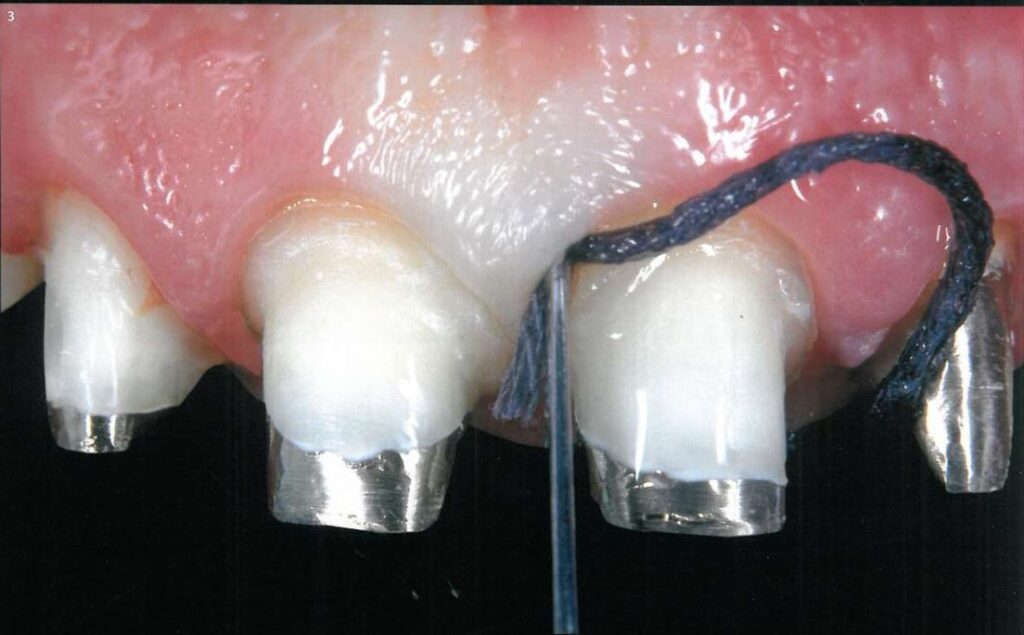

Sử dụng sợi chỉ thứ nhất với đường kính nhỏ (Ultrapak #000), ngâm vào dung dịch đệm Nhôm Chloride (Hemodent), vắt thật kĩ rồi đặt vào khe nướu bằng dụng cụ đặt chỉ đầu mảnh (Fischer’s Ultrapak #170) (H3).

Sợi chỉ thứ 2 lớn hơn (Ultrapak #1) được đặt tiếp theo sau đó, không nhất thiết phải nằm hoàn toàn trong khe nướu (H10, 11).